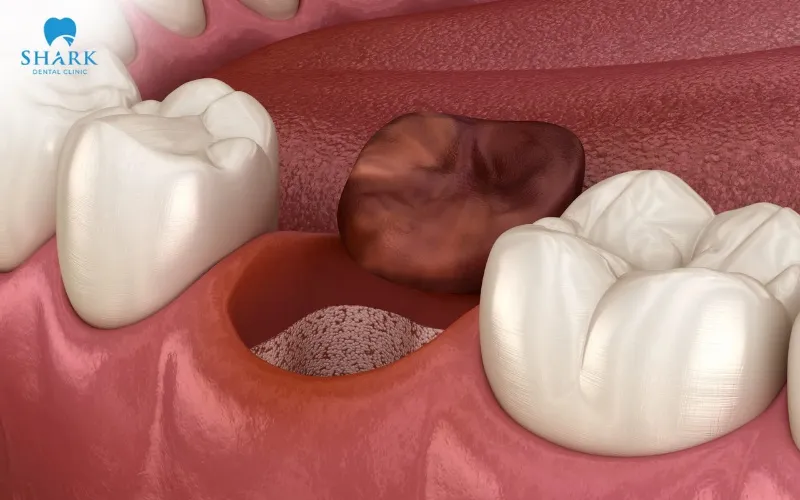

- A blood clot after tooth extraction will form in the empty socket, which is crucial for stopping bleeding and protecting the healing gum tissue.

- The blood clot has formed and needs to remain stable in the socket to protect the gum tissue and aid the healing process.

- The blood clot in the socket remains vital, so it must be carefully protected to avoid the risk of developing a dry socket.

- For wisdom teeth or multi-rooted extractions, a small hole may still be visible in the socket for several months; this is normal as the jawbone requires more time to regenerate.